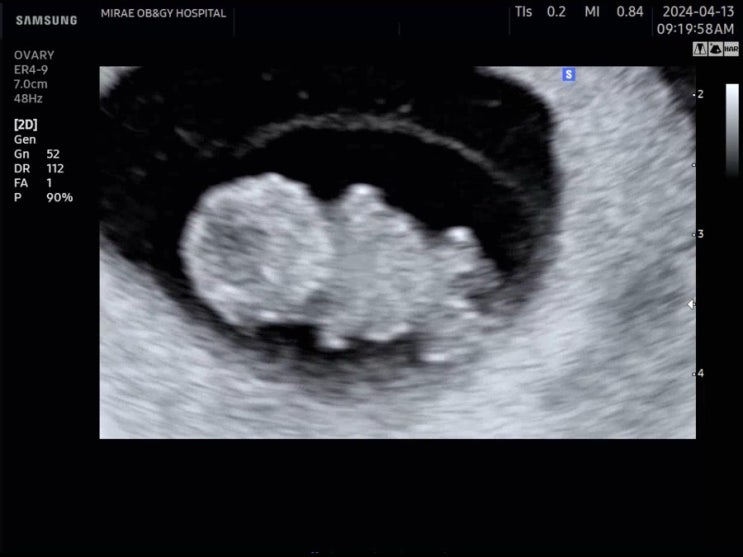

임신34주차 정기 검사, 강남 미래와 희망

34주차 5일 되던 날, 병원에서 검사를 하고 왔어요! 회사 반반차를 내고 남편과 병원에 방문! 9개월 임산부...